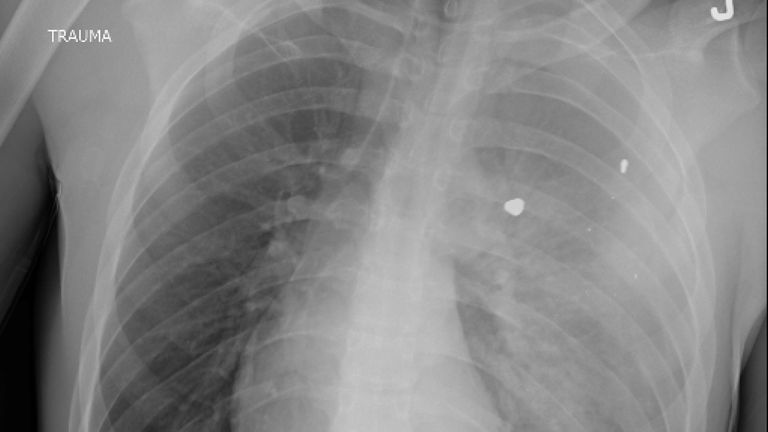

Dr Sam Ghali shared the chest X-ray of “a young boy suffering from a condition that is now the #1 cause of death in children and adolescents in the US” on X, formerly Twitter, asking his followers: “What’s the diagnosis?”

The picture shows the child’s chest with what appears to be foreign objects inside the lungs.